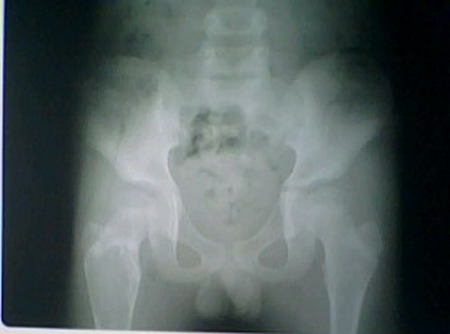

张某,男,11岁,外伤4天余

提示;骨囊肿,建议ct检查

儿童股骨上段一囊性膨胀性病变:应遵循一个思路,避免经验主义:病灶边缘可见硬化,特别是上缘比较明显,从这个角度出发,基本可以定义为良性肿瘤或肿瘤样病变,亦可基本排除骨囊肿的可能性,因为只有合并感染或外伤或术后的骨囊肿才会出现如此明显的硬化改变,其二,上述病灶内似是见到多发骨嵴样改变,亦不太支持骨囊肿,但发生于儿童的----骨干的---良性的---囊性的---膨胀性的----病变又可以是哪些呢:动脉瘤样骨囊肿,囊性骨纤可能是最大,其次是内生软骨瘤或非骨化性纤维瘤.动脉瘤样骨囊肿发生于骨端的比较多,且大多数可见轻度的(扶垛样)骨膜反应.非骨化性纤维瘤的硬化边要更明显,且病灶更偏于一侧.所以本例应多考虑------囊性骨纤的诊断.从影像结论来看,本人认为诊断方式较为妥当:右股骨上段良性囊性病变,考虑:囊性骨纤可能性大,不除外动脉瘤样骨囊肿或单纯性骨囊肿可能.

右股骨上段良性囊性病变,考虑:囊性骨纤可能性大,不除外动脉瘤样骨囊肿或单纯性骨囊肿可能.